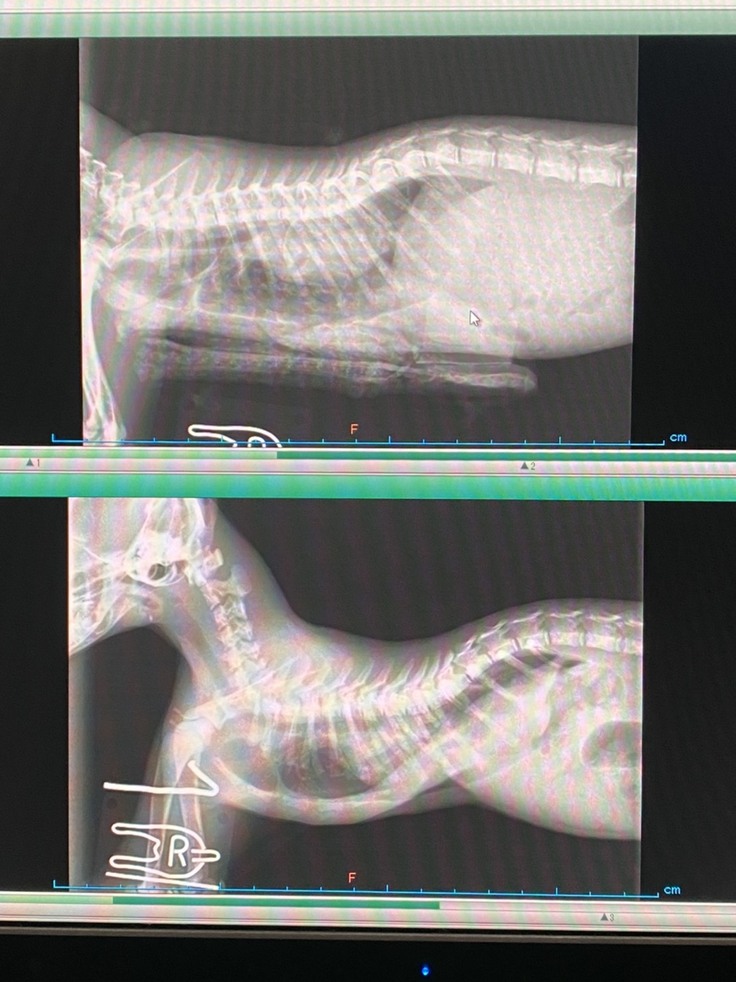

動物病院で検査のために撮られたレントゲン。

胸骨が大きく湾曲していることがわかります。

下が手術前、上が手術後のレントゲンです。

胸の骨がまっすぐになりました!